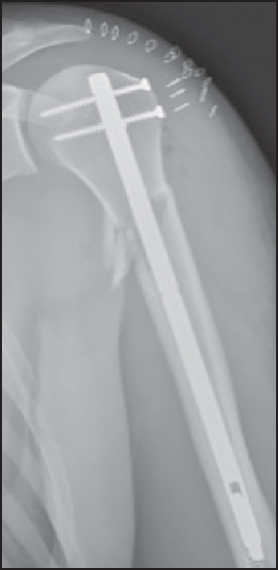

The patient underwent an open reduction and internal fixation with plate and screw (S3 Humeral Plate System; DePuy, Kirkel-Limbach, Germany) on the same day. Through a standard deltopectoral approach, a bare area on the anterior aspect of the humeral shaft, corresponding to the pectoralis major insertion site, was noticed. Further exploration revealed a complete rupture of the pectoralis major at the level of its insertion with retraction of the tendinous part. The tendon was identified and tagged with five Ethibond n° 5 sutures (Ethicon, Inc., Somerville, New Jersey). Reduction and internal fixation of the three-segment two-part proximal humerus fracture were performed with a plate [Figure 2]. The insertional site of the pectoralis major on the anterior aspect was debrided of remnant tendon, with minimal abrasion of the anterior cortex. The Ethibond sutures were then passed through the plate holes near the anatomical insertion site of the pectoralis major tendon. | Figure 2: Plain anteroposterior X-ray after open reduction and internal fixation on the first postoperative day

Click here to view |